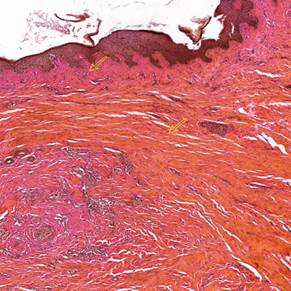

На препаратах, окрашенных кислым фуксином и пикриновой кислотой по методу Ван-Гизона (рис.3 и 4).

Рис.3. Коллагеновые пучки в дерме рубца до проведения лазерной терапии.

Окраска: кислый фуксин + пикриновая кислота (по методу Ван-Гизона). Ув.: 5. Желтыми стрелками показаны дефекты архитектоники в виде визуально неорганизованных утолщенных волокон коллагена. Примечание: составлен авторами по результатам данного исследования

Рис.4. Коллагеновые пучки в дерме рубца после проведения лазерной терапии.

Окраска: кислый фуксин + пикриновая кислота (по методу Ван-Гизона). Ув.: 5. Желтыми стрелками показаны сосочковый слой (верхняя стрелка) и сетчатый слой (нижняя стрелка), восстановившиеся после курса лазерной терапии.Примечание: составлен авторами по результатам данного исследования

Для выявления коллагеновых волокон в экстрацеллюлярном матриксе было оценено и проанализировано соотношение участков визуально организованных пучков волокон коллагена и визуально анизотропных участков. Данные, полученные в ходе исследования процентной доли, занимаемой визуально неорганизованным коллагеном от произвольной площади дермы, представлены в табл.2. Подобный метод подсчета позволяет нивелировать особенности индивидуального течения формирования рубцов. Таким образом, наиболее яркие результаты динамики исследуемого показателя наблюдаются в случаях 1 и 3 в группе с импрегнацией. В паре №1 процент снижения составил 56,5% (p=0,005), в паре №2 – 61,1% (p=0,005), в паре №3 также наблюдается снижение процентного соотношения на 56% (p=0,004), что является статистически значимой динамикой во всех случаях.

При анализе данных, полученных при оценке влияния терапии высокоинтенсивным лазерным излучением, была выявлена явная тенденция к восстановлению изотропной конфигурации пучков коллагеновых волокон в межклеточном веществе дермы рубцов с импрегнацией экзогенным пигментом и дермы рубцов без импрегнации.